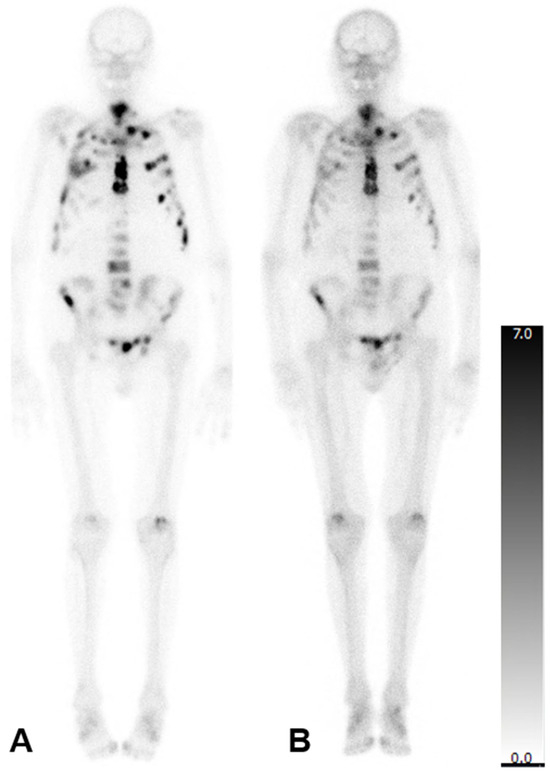

In patients who underwent three cycles of treatment, there was no statistically significant change in the mean aBSI (6.7 ± 5.2%; before: 4.5 ± 3.8%; p = 0.369), mean TTV (353.2 ± 369.2 mL; before: 356.1 ± 382.9 mL; p = 0.902), or mean SUVmax (562.3 ± 156.2; before: 801.7 ± 379.3; p = 0.149). The imaging of a representative patient case is presented in Figure 1.

Figure 1. Bone scintigraphy of a 77-year-old man with mCRPC. aBSI prior to 223Ra therapy was 7.5%, TTV 1112.20 mL and SUVmax 388 (A). After three cycles of 223Ra therapy, aBSI was 6.7%, TTV was 97.03 mL, and SUVmax was 293 (B).